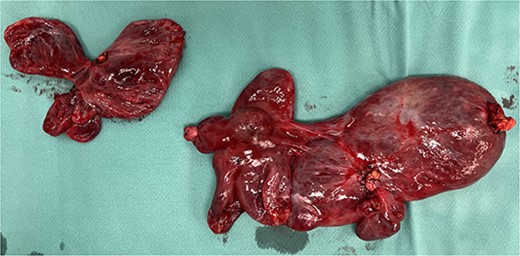

A 59-year-old woman presented to the abdominal surgery unit of our hospital for a dimensional increase of known epigastric multiloculated cystic formation detected on computed tomography (CT)-scan follow-up, with a maximum diameter of~20 cm (Fig. 1). Her medical history included breast and colon adenocarcinoma and scapular melanoma, all of which were surgically treated in addition to chemo, hormone and radiation therapies. The patient was asymptomatic. Blood tests were unremarkable. At explorative laparotomy, a voluminous multi-chambered and well-vascularized cystic formation was found (Fig. 2). Surgical excision was performed after ligation of the two vascular peduncles located in the small omentum (Fig. 3). Histological findings showed an angioleiomuscular tumor with cavernous aspects and uncertain potential for malignancy. The patient was discharged on postoperative day 4 without complications. At follow-up visits at 1, 3 and 6 months, the patient was in good condition with no disease recurrence.

Intraoperative findings showing the multiloculated epigastric tumor.

Surgical piece illustrating the two vascular pedicles of the neoformation.